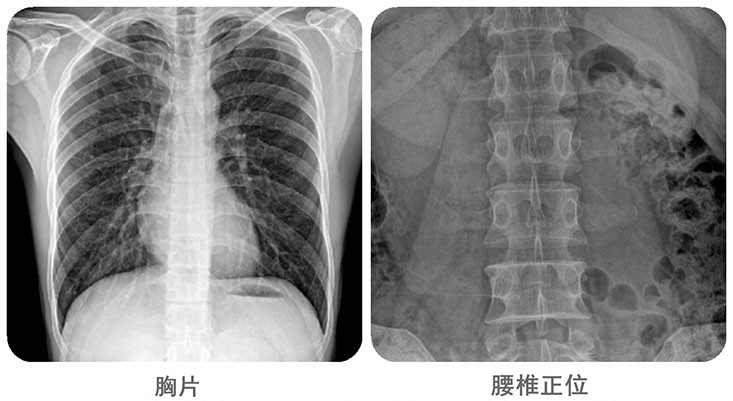

清晰影像,便于臨床診斷。移動DR能夠滿足人體的頭部、四肢、胸腔、脊柱、腰椎、腹部等全身多部位的數(shù)字化攝影需求。